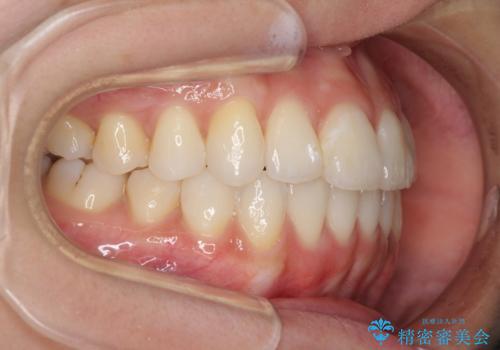

インプラント治療は当初の狙い通り、矯正治療期間中に行い、スムーズに処置を進めることができました。

歯並びが整ったことで治療前に認められた歯肉炎は全くなくなり、患者様には大変満足していただきました。